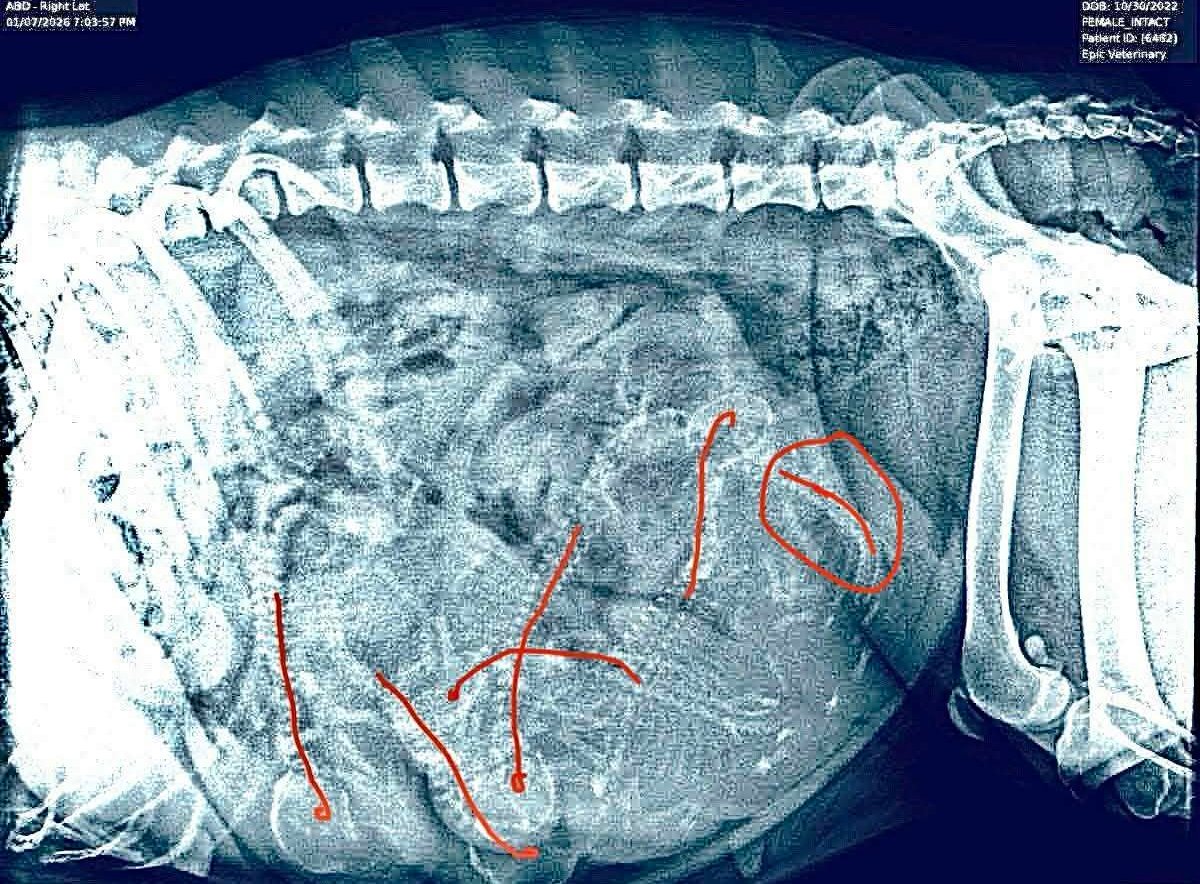

Update: 10 January 2026. Six puppies confirmed on X-Ray. We will be welcoming a new batch of Snarfs early next week.